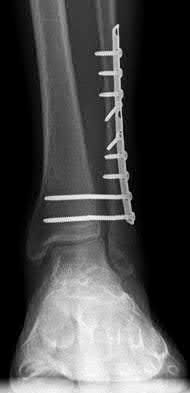

Figure A shows a patient after an open reduction and internal fixation of a bimalleolar ankle fracture.

Egol et al showed that by nine weeks, the total braking time of patients who had undergone fixation of a displaced right ankle fracture returns to the normal, baseline value.

Egol et al, also found that appropriate braking time returns at a point 6 weeks after initiation of weightbearing after treatment of lower extremity long bone and periarticular fractures, as examined with a driving simulator. No differences were seen in return of braking time between periarticular fractures and long bone injuries.